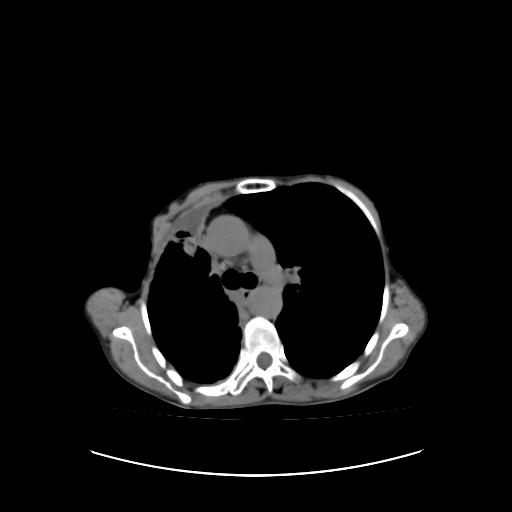

标题: CT16930:女 59 胸痛6个月 胸水脱落细胞学见瘤细胞 [打印本页]

标题: CT16930:女 59 胸痛6个月 胸水脱落细胞学见瘤细胞

右侧胸膜增厚,局部呈结节状增厚,右侧胸腔少量积液。双肺未见确切肿块影。纵隔未见淋巴结肿大。气管、支气管通畅。考虑右侧胸膜间皮瘤(恶性?)可能性大。不除外癌性胸膜炎。

右侧胸廓塌陷,右侧胸膜广泛增厚并见多发胸膜结节,右侧少量胸腔积液并包裹。

右侧广泛胸膜增厚,局部呈结节状增厚,右侧胸腔少量积液。双肺未见确切肿块影。纵隔未见淋巴结肿大。气管、支气管通畅。考虑右侧胸膜间皮瘤(恶性?)可能性大。支持!